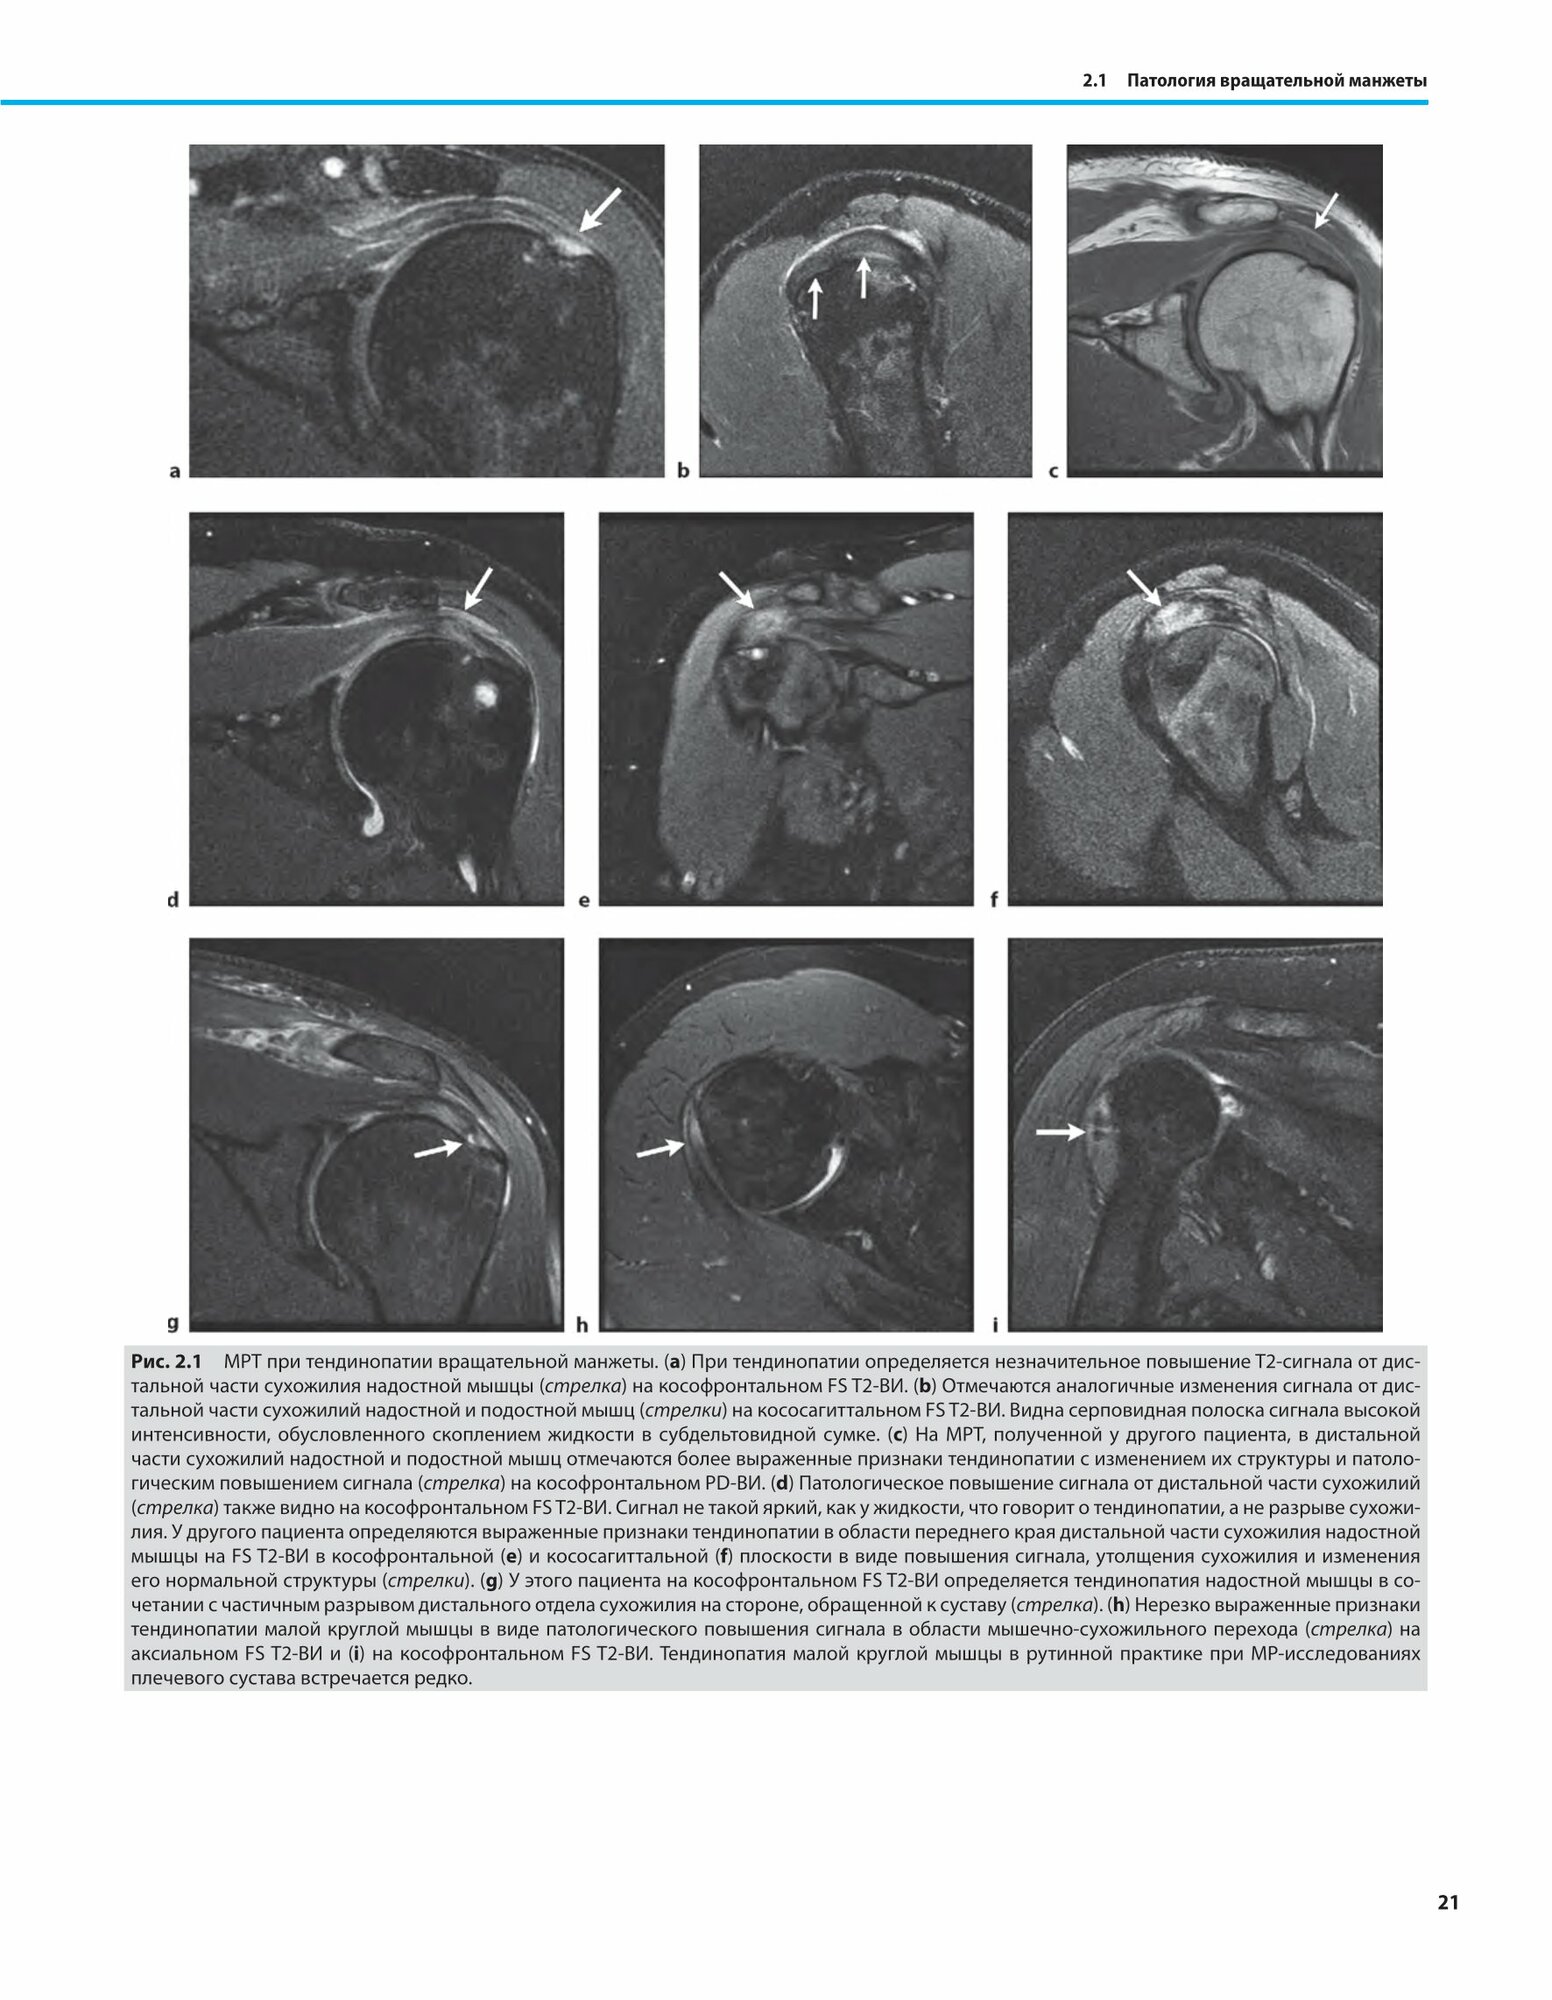

МРТ костно-мышечной системы. Дифференциальная диагностика (Холленберг Г. М.; Вейнберг Э. П; Мейерс С. П.); МЕДпресс-информ, 2018

Издание посвящено МРТ-диагностике патологии опорно-двигательного аппарата, включая врожденные, приобретенные, метаболические, воспалительные, инфекционные и гематологические заболевания, а также опухоли и опухолеподобные образования. Книга состоит из вводной главы и основной части, текст которой разделен на два дифференциально-диагностических ряда в табличном формате (всего 49 таблиц): один - на основании локализации (плечевой сустав, локтевой сустав, лучезапястный сустав и кисть, тазобедренный сустав, коленный сустав, голеностопный сустав и стопа и различные анатомические зоны костей и мягких тканей), другой - конкретных MP-признаков, особенно важных изменений, характерных для патологии той или иной локализации. Комментарии в таблицах содержат описание MP-симптоматики, дополненное результатами других методов визуализации и наиболее важными данными по этиологии, клинической и патогистологической картине описываемых поражений.